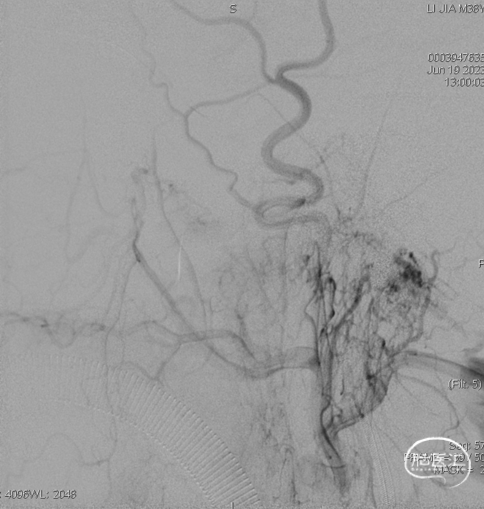

术后造影见瘘口不显影。

术后右侧颈总造影,未见向瘘口供血。

术后铸胶形态及CT下铸胶位置,可见瘘口位于左侧舌下神经管区域。

术后1个月、3个月、5个月临床随访,患者左眼外突及结膜充血水肿完全缓解,无新发神经系统阳性体征。